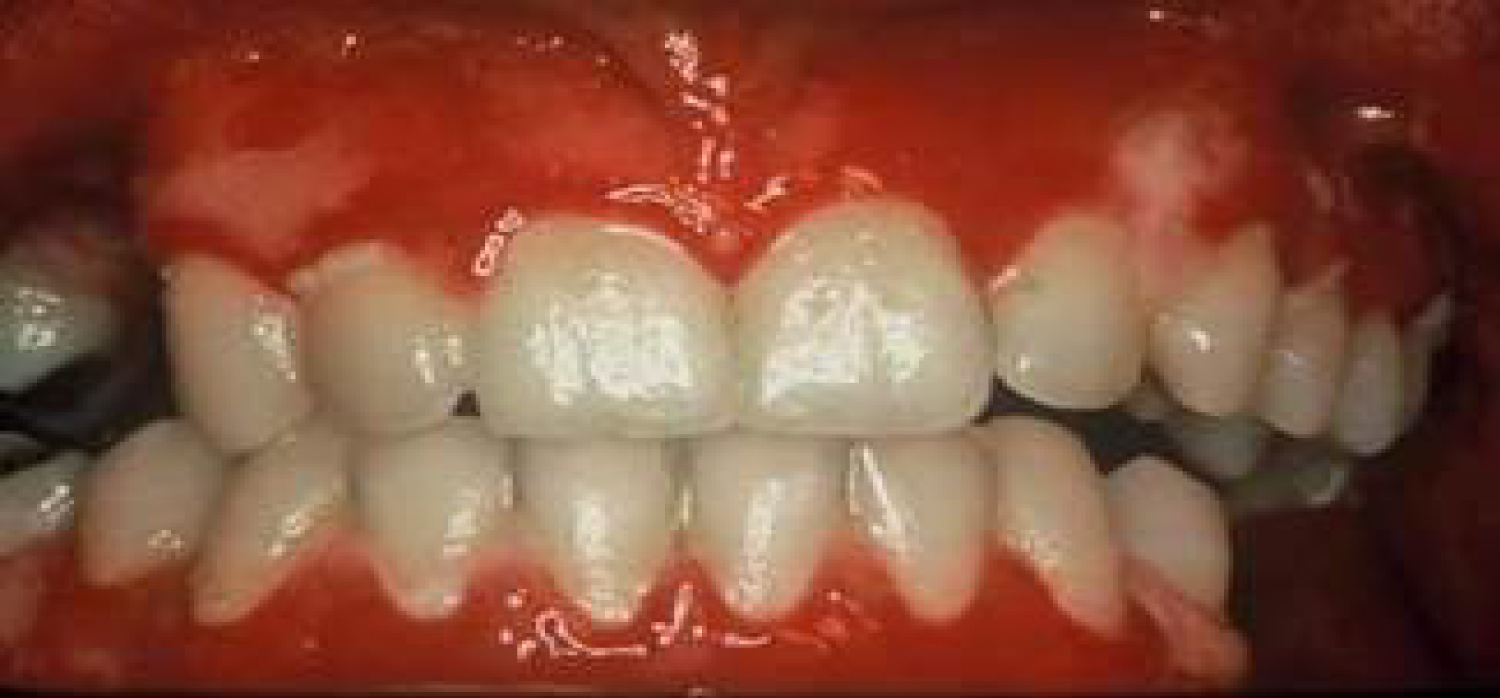

Calcium channel blockers

These agents are extensively used in the treatment of a several cardiovascular diseases. As saliva secretion is closely related to intracellular calcium concentration, why blockers of calcium channels such as Diltiazem, Nifedipine and Verapamil will cause xerostomia and further oral consequences is generally understood [5]. Calcium channel blockers have been known to cause gingival overgrowth since the 1980's [1]. However, since calcium channel blockers are so commonly administered, it is extremely hard to verify the actual incidence of gingival enlargement resulting from the usage of these drugs [4]. An example of the overgrowth induced by calcium channel blockers can be seen in Figure 1. In a study performed in order to observe the adverse drug reactions of Nifedipine, it has been demonstrated that the drug caused gingival hyperplasia in 20% of users [2]. Nifedipine acts by inhibiting the process of apoptosis in keratinocytes and prolonging cell life, and as such leading to an epithelial enlargement of the gingiva [6]. Another mechanism of action for Nifedipine has been suggested to be the inhibition of macrophage-induced death of gingival fibroblasts [7]. Another study was performed in order to observe the histological changes generated by Nifedipine in hypertensive animals. Findings have shown alterations in the parotid glands, together with a mild dilation of the vessels and infiltration of inflammatory cells [8].

Figure 1: Gingival hyperplasia caused by calcium channel blockers. View Figure 1